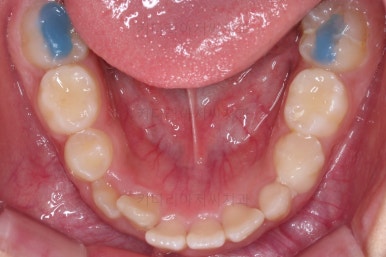

1. 초진

초진 시 입안의 모습입니다.

가장 눈에 띄는 건, 아랫니가 윗니보다 앞에 나와있는 부정교합인데요.